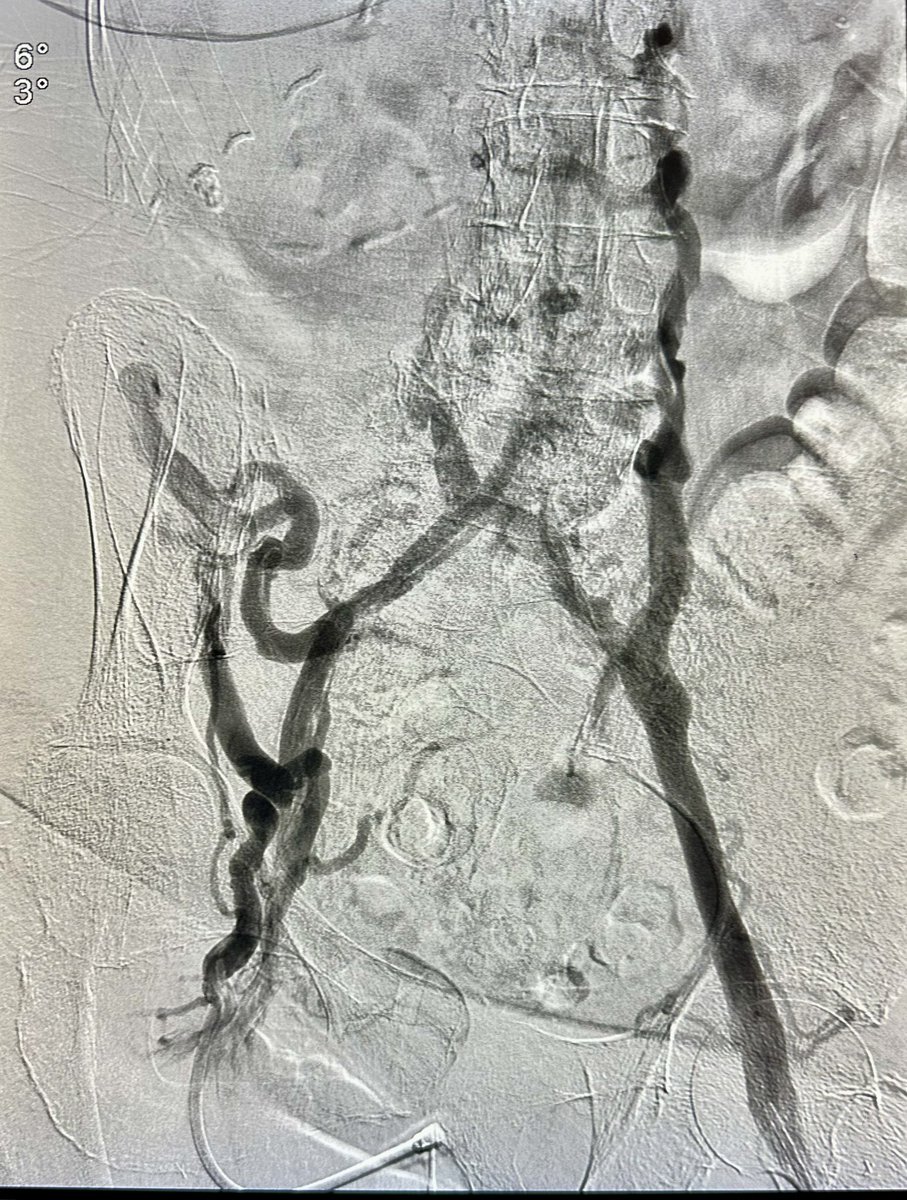

Pt with h/o LLE DVT rxed with surgical thrombectomy remotely, with B/L LE edema and ulcers. Had CTO of infrarenal IVC and bilateral iliac veins, treated with IVUS venoplasty, double barrel stenting of IVC to bilateral EIV and RCFV @OEISociety @VenousForum @VIVAPhysicians

dr_ashishg's tweet image. Pt with h/o LLE DVT rxed with surgical thrombectomy remotely, with B/L LE edema and ulcers. Had CTO of infrarenal IVC and bilateral iliac veins, treated with IVUS venoplasty, double barrel stenting of IVC to bilateral EIV and RCFV @OEISociety @VenousForum @VIVAPhysicians